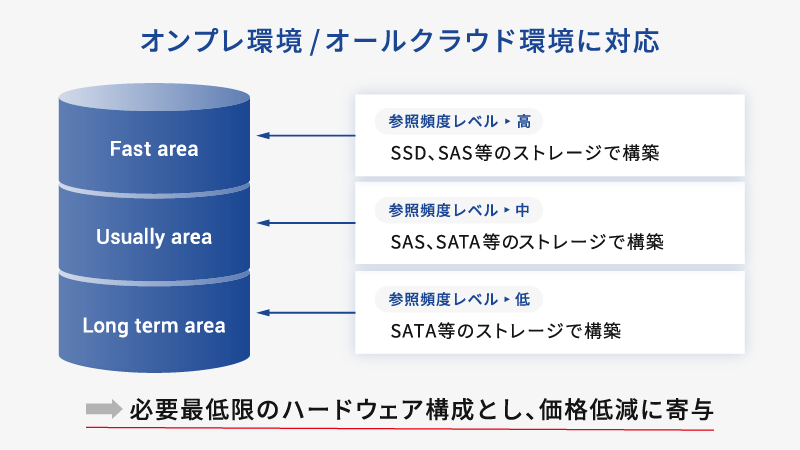

アーカイブ3層構造

アーカイブ3層構造

画像参照頻度を考慮し、ストレージ構造を高速・中速・低速とした3層データ管理を実現。

高価な高速ストレージの使用を最小限に抑え、全体的なストレージコストを効率的に管理しながら、必要なデータに迅速にアクセスできる環境を構築いたします。